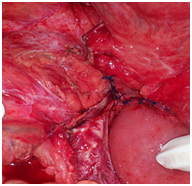

All the patients were explored urgently by midline incisions. The different types of hernia found were through: Paranormal orifice: 3 left paraduodenal (Figures 2) (Figure 3A) (Figure 3B), 2 right paraduodenal, 1 intra-mesosigmoidal and 1 retrocecal. Abnormal pathologic orifice: 2 trans-mesenteric (Figures 4A-4C), 1 in the posterior cavity through a colo-omental dissinsertion hole Figure 5 and 1 trans-omental. The Reduction of the herniated viscera was never a problem but a bowel necrosis was found in two cases, which required dilatation of the hernial orifice and resection of 1, 25m and 60cm of small bowel with immediate restoration of continuity. The closure of peritoneal fossae or an abnormal orifice was done easily with a resorbable suture (Table 2). We had no death in our patients. Two cases of wound infection were reported classified Grade I in the Clavien-Dindo classification of surgical complications. These patients were treated by antibiotics and had local treatment. The length of hospital stay was 8 days (3-11days). In the follow-up, there was no recurrence.

Figure 3B Closure of a left paraduodenal hernia’s sac.